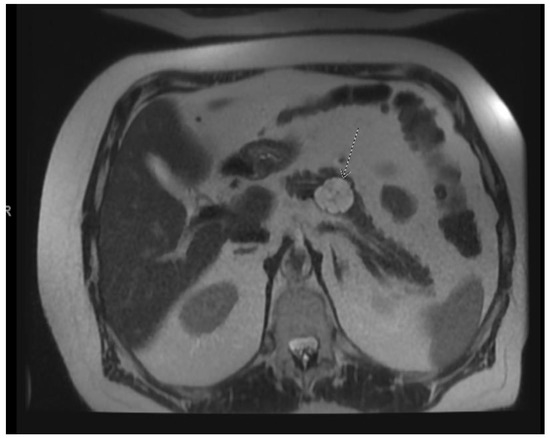

Figure 1.

EUS image of the mural nodule (labeled solid component) in a mucinous cyst.